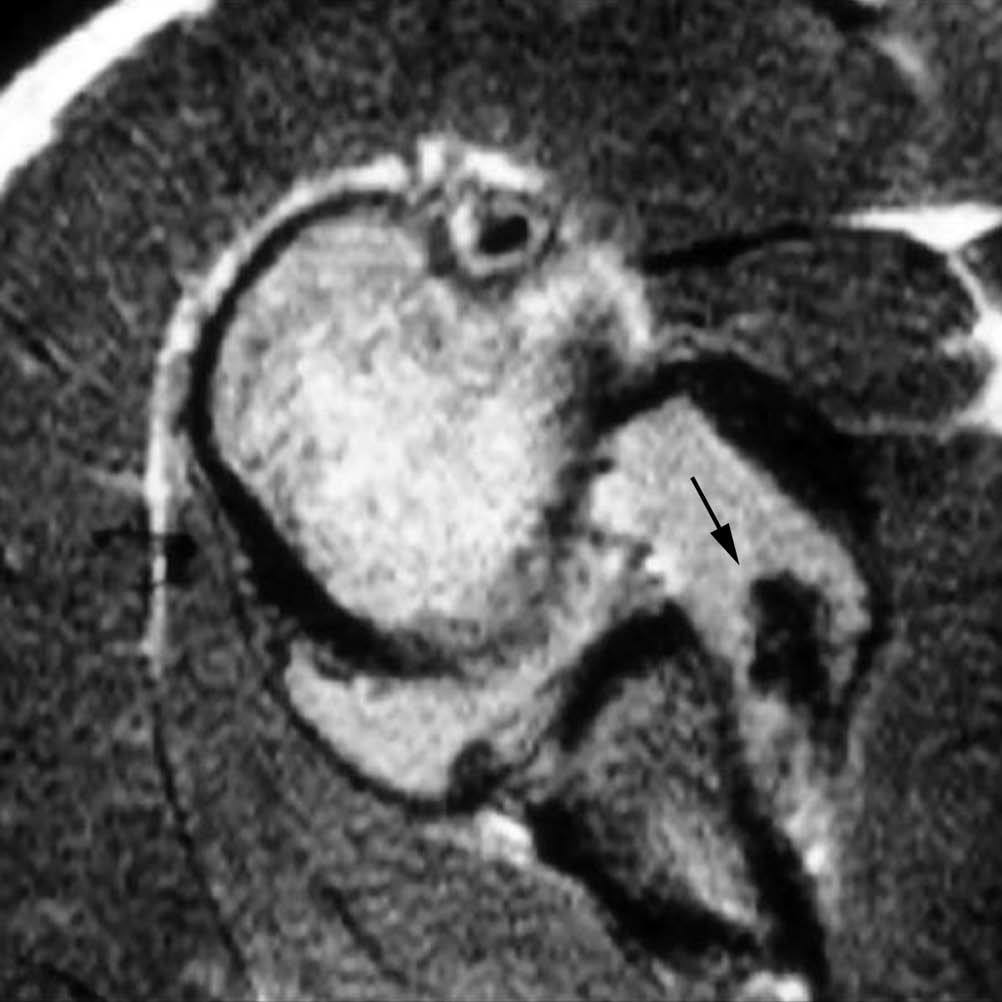

Lesiones de la banda anterior del ligamento glenohumeral inferior

La banda anterior del LGHI puede lesionarse en su inserción en el borde glenoideo anterior (lesión de Bankart descrita anteriormente), en su inserción humeral o bien en ambas. La lesión en la inserción humeral recibe el acrónimo de HAGL (humeral avulsion of the glenohumeral ligament)21 (fig. 19). Si se acompaña de una avulsión ósea en la inserción humeral, la lesión se conoce con las siglas de BAGHL (bony avulsion glenohumeral ligament). Si la lesión afecta a ambos puntos de inserción, se la conoce por el nombre de floating AIGHL. Esta última es una combinación de una lesión de Bankart y una lesión de HAGL22-26.

Fig. 19.--Lesión de HAGL (humeral avulsión of the glenomumeral ligament). Imagen axial T2 donde se puede apreciar un desprendimiento de la banda anterior del ligamento glenohumeral inferior (LGHI) a nivel de su inserción humeral (flecha).